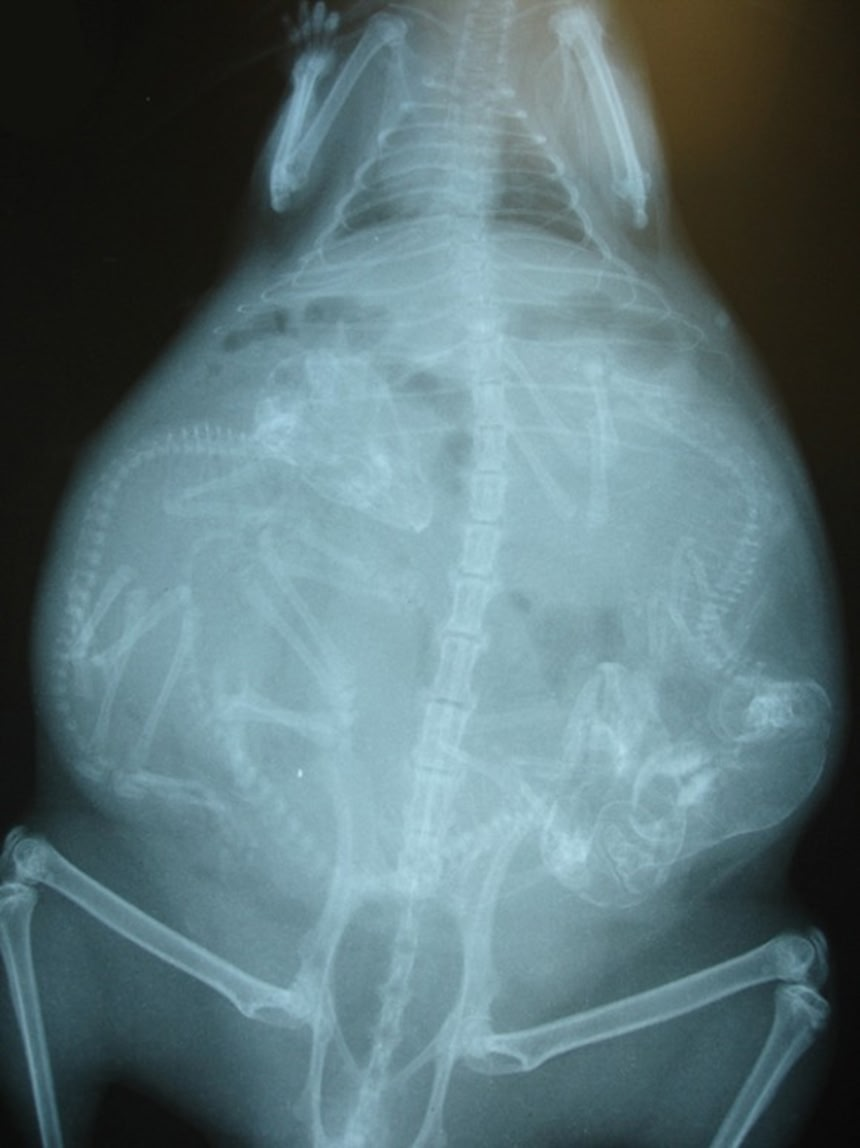

この画像を大きなサイズで見る6. モルモット

出産直前に、お母さんのお腹の中に何匹の赤ちゃんがいるかの確認のためのレントゲンだよ。

何匹いるか確認しておかないと、死産で残ってしまったりしたらお母さんの体が危険でしょ?

って元スレのコメに書いてあったよ。

人間は基本一人だけど、三匹四匹まとめてお腹に入れてるのはレントゲンで見るとやっぱ驚く。

結構ごちゃごちゃっと入ってんのね…

モルモットは整頓されてる